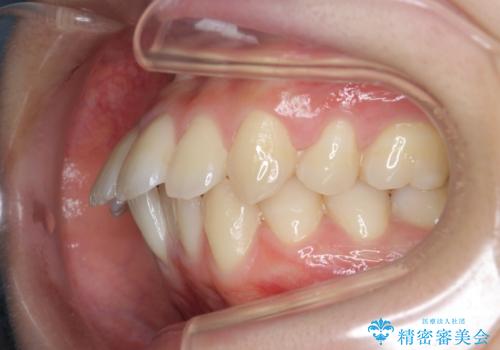

突き出た前歯の改善!マウスピースで再矯正

- 5年前にワイヤー矯正治療を終了したが、突き出たように見える前歯の仕上がりが気に入らず、再矯正治療を希望され来院されました。

マイクロインプラントを用いた遠心移動とIPRを行うことによる前歯の突出感の改善をマウスピース矯正治療で計画します。

突出していた前歯の角度が大きく改善し、審美的な仕上がりに満足いただくことができました。